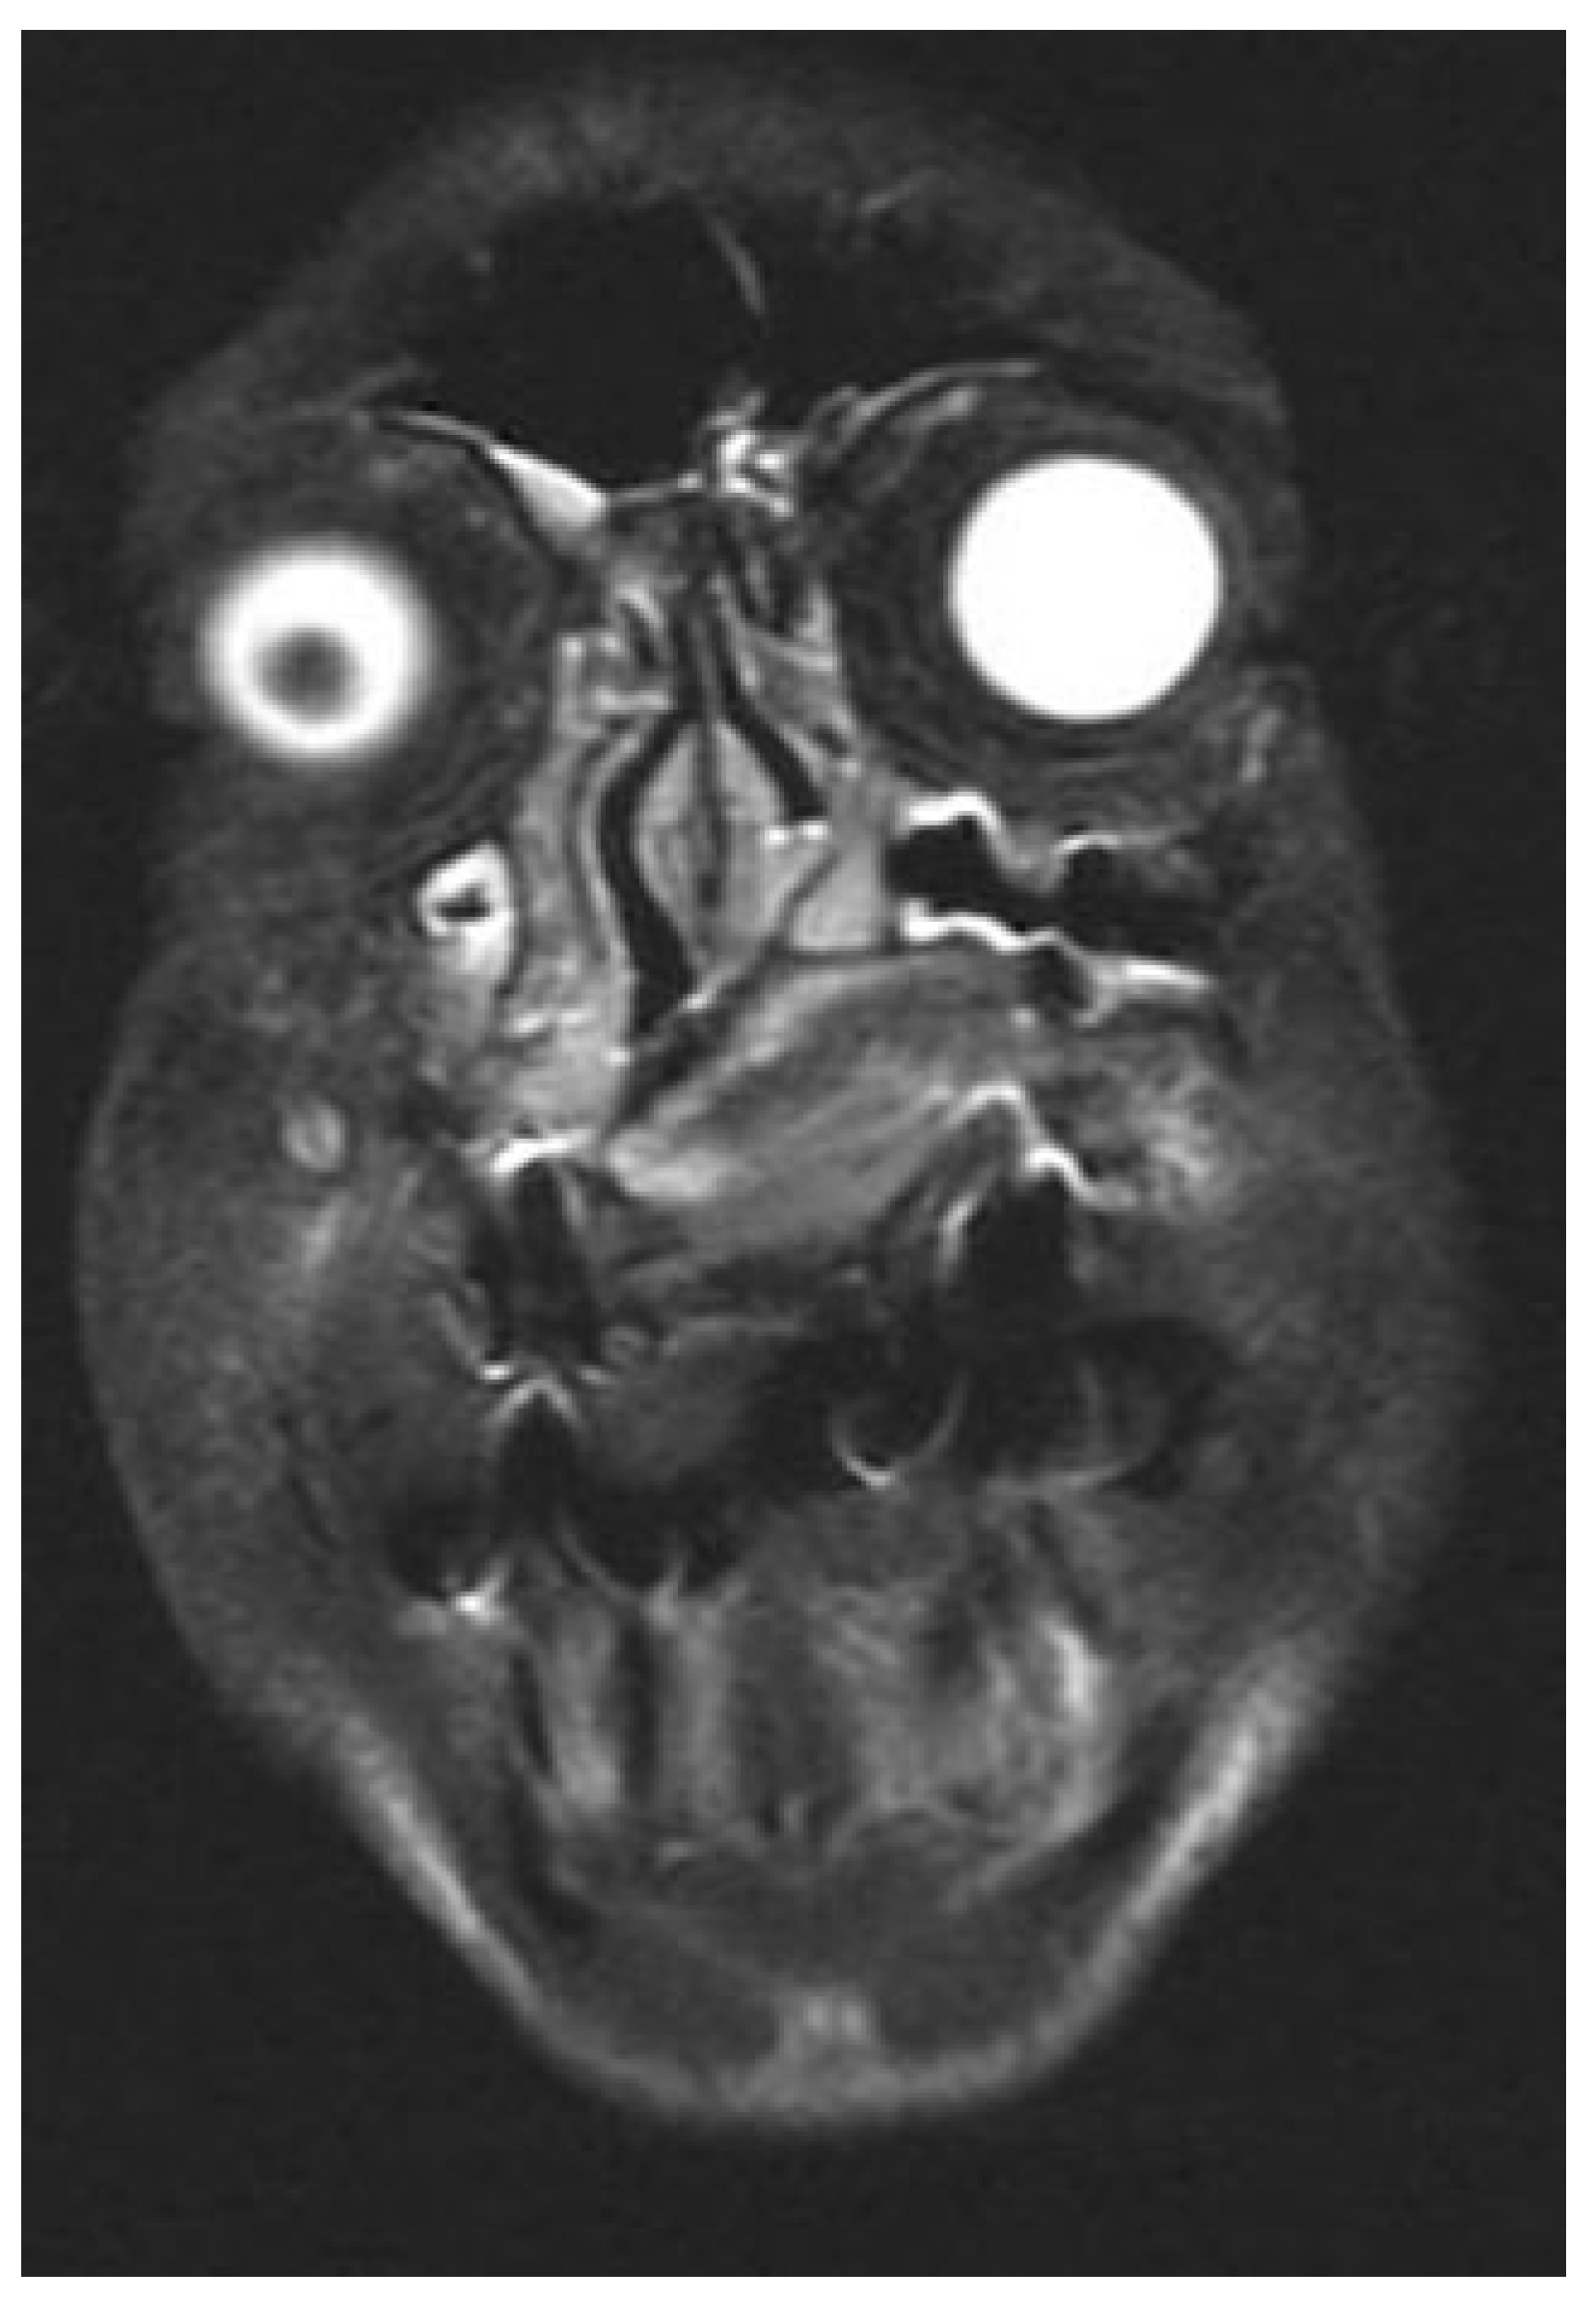

Once in the operating room, the kind of intubation should be individualized. For unilateral tumors, intranasal intubation is preferred to improve the intraoral visualization and facility tumor resection. Submental intubation represents an effective alternative especially with tumors affecting both nostrils. This technique places the endotracheal tube away from our surgical field and improves the tumor visualization. In the surgical technique, first, a free margin is delimitated on the palatine mucosa reaching the bone layer and a palatine osteotomy is done using an oscillating saw (Figure 1). Next, a vestibular maxillary approach is done and microplates are fixed at both sides of the maxilla to guarantee the correct reposition of the maxilla at the end of the procedure. Screws and microplates are removed and a Le Fort I osteotomy is performed. This represent the most critical point of the approach and attention must be directed to the piriform aperture, lateral nasal walls, and the septum in order to make the cuts without entering into the tumor. Preoperative imaging is crucial to determine the intranasal extension of the tumor and decide the level of the Le Fort osteotomy (Figure 2). Vertical extension of the tumor determines the most limiting factor and tumors with high intranasal extension may not be candidates for this kind of approach, as the risk of tumor disruption is higher in these cases.

Figure 2. Preoperative CT showing the intranasal extension of the tumor.